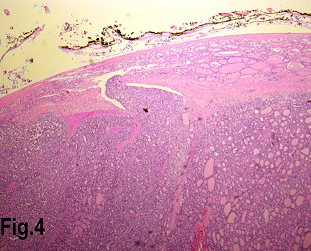

Solitary benign adenomas were found in 23 cases, the peak frequency was fourth and fifth decade. Female accounted for 12 cases (70.5%) for follicular adenoma (Figure 2) and 3 cases (50%) for Hurthle cell adenoma. Thyroid malignancy and it was reported in 62 cases. Papillary carcinoma (Figure 3) was the most common type of thyroid malignancy found in 44 cases (71%) followed by follicular carcinoma (9.6%) (Figure 4), medullary carcinoma (1.6) and poorly differentiated carcinoma (1.6%) (Table 3). The peak incidence for patients with thyroid malignancy in this series was third decade and male to female ratio was 3.7:1.

Figure 4.Low power view showing a follicular carcinoma with capsular invasion. (Hematoxylin & eosin, original magnification ×200).